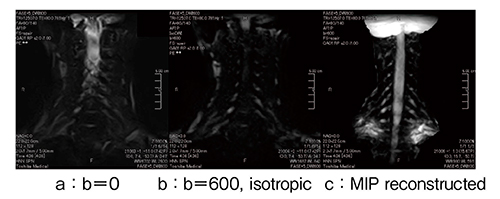

高分解能撮像が可能になることを生かし,図1に示すようにT2*の短い組織が多い胸部での応用1)として,呼気と吸気の描出能を比較し,呼気の描出能が優れることを確認している。また,関節系やブレストのインプラント膜の描出などの新たな臨床応用についても検討中である。

図1 呼吸による肺野の描出能の差